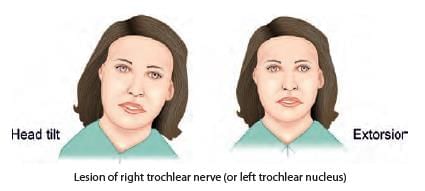

A patient presented with squint in right eye, as shown below. Identify the nerve lesioned in this case: (NEET-PG 2020p)

A child presented with left sided head tilt. On head straightening, there is right hypotropia, which increases on tilting head to right side. Which of the following muscle is paralysed? (AIIMS June 2020)